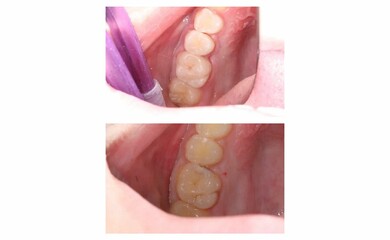

В карусели кейс врача стоматолога-терапевта Колиш Максима Петровича:

Пациент обратился с жалобами на застревание пищи между зубами, реакцию на сладкое и холодное.

При осмотре обнаружен контактный кариес на зубах 26, 25. Лечений в один визит. Восстановление функциональности композитной реставрацией.